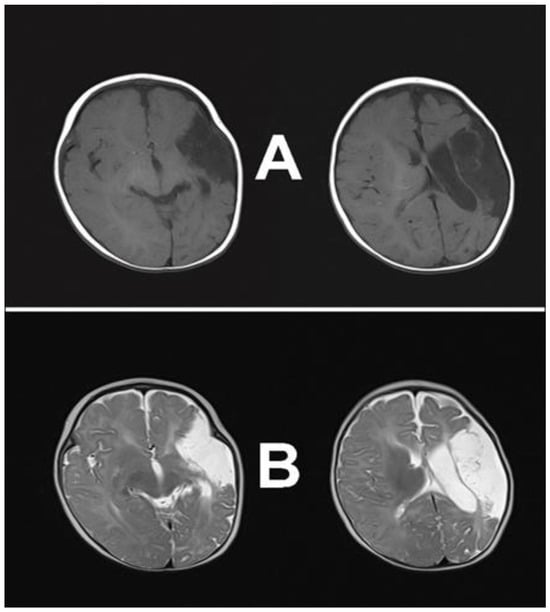

2. Case Presentation

2.1. Case Report